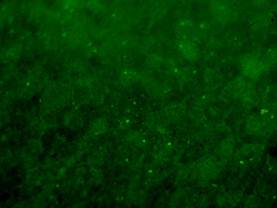

Рис. 4.8.5 Специфическое свечение вирусинфицированных нейронов при бешенстве: а – корова, б – лиса, в – собака, г – человек

в)

г)